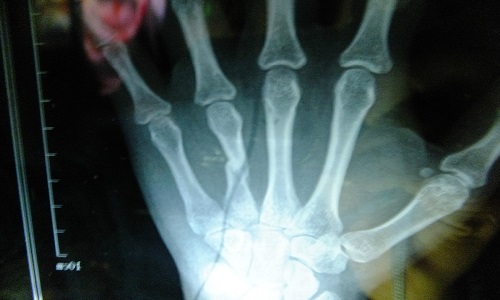

3.骨折的特有体征

(1)畸形 骨折端移位可使患肢外形发生改变,主要表现为缩短、成角、延长。

(2)异常活动 正常情况下肢体不能活动的部位,骨折后出现不正常的活动。

(3)骨擦音或骨擦感 骨折后两骨折端相互摩擦撞击,可产生骨擦音或骨擦感。

以上三种体征只要发现其中之一即可确诊,但未见此三种体征者也不能排除骨折的可能,如嵌插骨折、裂缝骨折。一般情况下不要为了诊断而检查上述体征,因为这会加重损伤。

骨折病人的典型表现是伤后出现局部变形、肢体等出现异常运动、移动肢体时可听到骨擦音。此外,伤口剧痛,局部肿胀、淤血,伤后出现运动障碍。